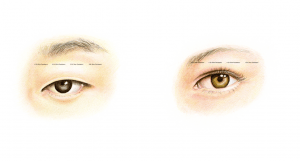

The basic, anatomical differences in Asian and Caucasian eyelids

Anatomically speaking, there are a number of subtle differences in the upper eyelids of East Asians compared to the eyelids of Europeans and Sub-Saharan Africans. While some East Asians have an eyelid crease and some do not, there is also a large variation in the skin fold position of the upper eyelid in East Asia. The position of the upper eyelid skin fold can vary from 1 mm above the lash line to approximately 10 mm, but when people come to the ELZA Institute for oculoplastic surgery, the changes they desire is very individual, but usually the goal is to obtain a more energetic, youthful and natural look.

It is important that the doctor performing this procedure has special expertise in this area. Oculoplastic surgeons are ophthalmologists who specialize in eyelid surgery and who – like no other – understand the complex relationship between the eye and the eyelid. For example, an assessment of the different aspects of the eyelid such as eyelid height (the position of the lash line relative to the pupil), the amount of skin, the presence or absence of a so-called eyelid crease (the line above which the skin fold forms), the shape of the epicanthal fold, and the position and shape of the eyebrow should all be made preoperatively. It is also important to look for signs of dry (or wet) eyes, as this helps to prevent eye complaints after the procedure.

Photos from the past (around the age of 20–25 years) can give a good indication of the natural look of the eyelids and eyebrows – if too much tissue is removed, then it results in eyelids with an unnatural look.